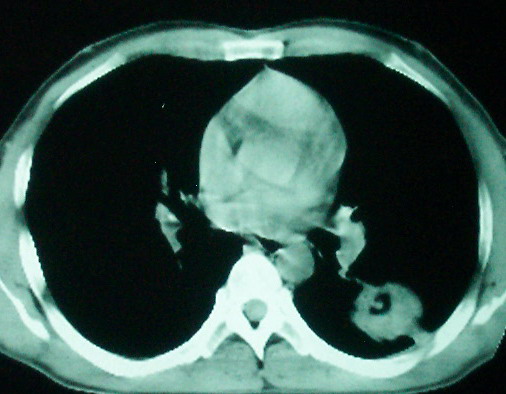

m      37y      发热   咳脓痰月余      ct肺脓肿但住院抗炎治疗后双肺内结节不知该如何解释

治疗后见左肺下野病灶较前缩小但双肺内结节影似无变化请较各位老师该如何下结论    治疗前wbc14.5 治疗后wbc 11.0

左下肺病灶除了明显的厚壁空洞 气液平外,明显见壁结节,另两肺多发小结节,综合考虑:左下肺周围性肺癌伴肺内转移.

鳞癌肺肺转移:厚壁空洞,洞壁厚薄不均,内似有壁结节,肺脓肿临床有无提示,血像如何?病灶周围很干净,没有明显渗出,很勉强?

如果你仔细的同层面对比,你会发现所有的病灶均有比较明显的吸收、缩小。病变的形态,特别是脓肿的形态、壁的厚薄、内壁均有很大的变化,均在往好的方面发展。与临床症状、血像均符合,治疗效果比较显著,就是肺脓肿并双肺的化脓性炎症灶。